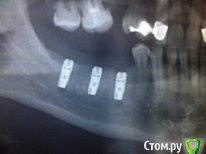

su_iri Опубликовано 18 августа, 2015 Поделиться Опубликовано 18 августа, 2015 Здравствуйте,у меня возникло осложнение после имплантации 3 имплантов в нижней правой стороне челюстина 3 день после того, как отек спал появилось онемение небольшой полоски от нижней губы до подбородкачувствительность пропала не полностью, а только частично, те имеет место ощущение ватности кожи и легкое покалывание, как при затеканиисегодня 4 день после операции, обращалась к хирургу, производившему имплантациюона сделала снимок, осмотрела и сказала, что имплант до нерва не дошел и это просто от гемотомы, в течение 10 дней должно пройти и нужно принемать нейромультивит пожалуйста, посмотрите фото снимка, реально ли нерв не задет и может ли это ощущение пройти при прохождении гемотомы. и какие варианты развития, если это не так Спасибо Ссылка на комментарий

diesel87 Опубликовано 18 августа, 2015 Поделиться Опубликовано 18 августа, 2015 Близость к нерву у 1 и 3 импланта прослеживается, надо четче снимок или кт, если есть ощущение что только местами занемело, скорее всего вернется чувствительность. 1 Ссылка на комментарий

su_iri Опубликовано 19 августа, 2015 Автор Поделиться Опубликовано 19 августа, 2015 Близость к нерву у 1 и 3 импланта прослеживается, надо четче снимок или кт, если есть ощущение что только местами занемело, скорее всего вернется чувствительность.Большое спасибо за ответсделала кт, если сможете, посмотрите, пожалуйстаhttp://www.fayloobmennik.net/5395032сегодня была еще у одного хирурга, сказали, что задний имплант давит на нерва имплант задний может влиять на область подбородка?и если это так, какие варианты решения проблемы?если имплант удалить, чувствительность восстановится?спасибо Ссылка на комментарий

krokomot Опубликовано 19 августа, 2015 Поделиться Опубликовано 19 августа, 2015 На кт есть здавление последним имплантом нерва, думаю нужно выкрутить и поставить белее короткий или вообще пока туда не ставить. Ссылка на комментарий

Bier Опубликовано 21 августа, 2015 Поделиться Опубликовано 21 августа, 2015 На КТ мы видим лишь имплантат, который чуть-чуть заходит в область, где находится нерв. Помимо нерва там еще сосуды. И сама картинка не означает, что нерв в этом месте травмирован. Локализация парестезии скорее говорит о травме в области ментального отверстия. 1 Ссылка на комментарий